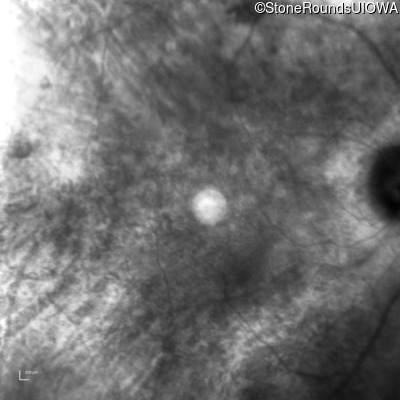

Age at visit: 53 years

OD OS

This 53 year old woman first came to attention when she had difficulty walking down stairs. A few years later she noticed difficulty seeing in dim light.

Diagnosis & molecular findings

AD Retinitis Pigmentosa PRPH2 Pro216Ser CCT>TCT   AD